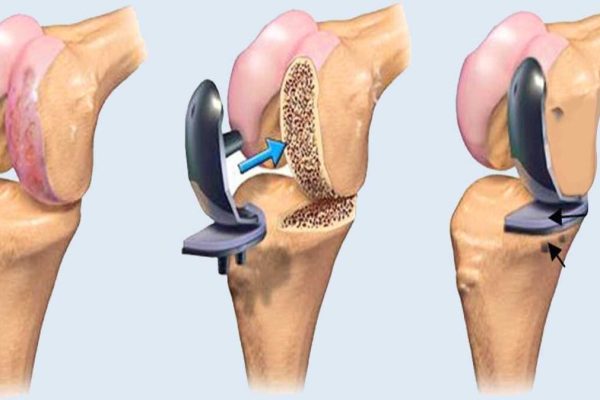

Joint pain, fractures, and sports injuries can limit your ability to live fully. At SALAM Shah Alam Specialist Hospital, our Orthopaedics & Traumatology team is here to help you move better—whether you’re recovering from an injury or managing a long-term condition.

This specialty focuses on the bones, joints, ligaments, muscles, and tendons. From diagnosing pain to performing surgery or rehabilitation, our goal is to get you back on your feet with minimal discomfort and long-term relief.